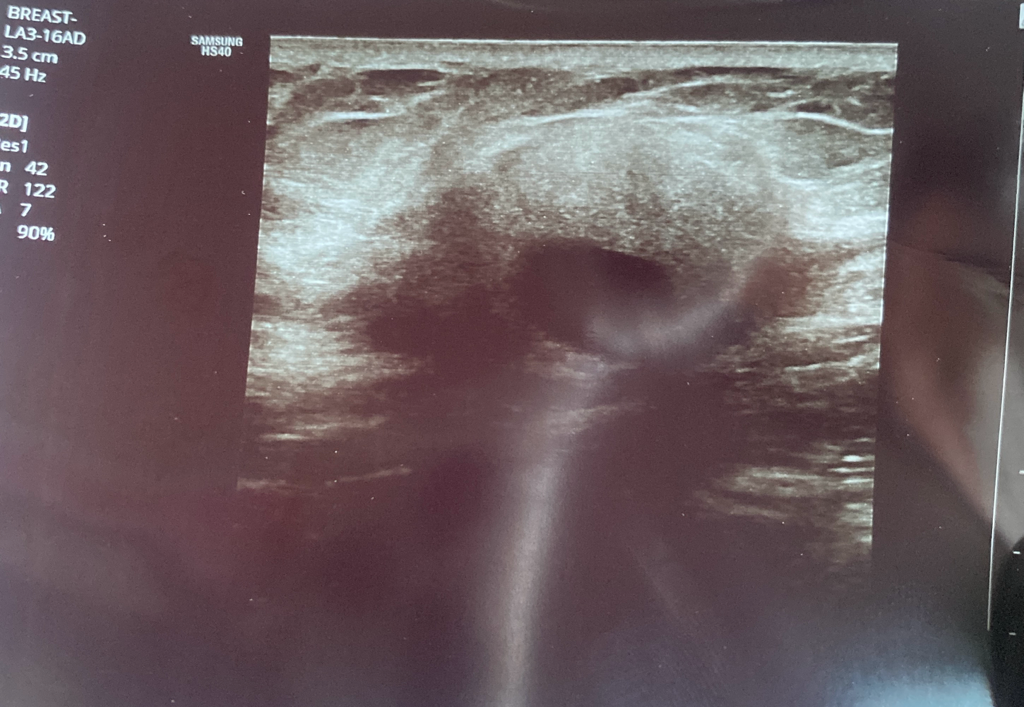

초음파 혹 모양 좀 봐주세요.

표피낭종이나 지방종일 가능성 있을까요?

오른쪽 쇄골 뼈 밑이고 크기는 3cm정도입니다.

아프지않고 단단한 편 입니다. 피부 겉에 검은 구멍 같은 것도 없는데 표피낭종일 수 있을까요?

또한 이렇게 동그란 모양도 악성 종양일 가능성이 클까요?

지금은 조직검사 결과 기다리는 중인데 결과가 빨리 나오지않아 잠도 자지 못하고 있습니다. 도와주세요 선생님들..

• 안녕하세요. 강성주 의사입니다.

표피낭종 이나 지방종의 양상과는 거리가 멀어 보입니다.

우선 양성종양의 가능성이 높기 때문에 조직검사 결과를 기다려 보시는 것이 좋겠습니다.